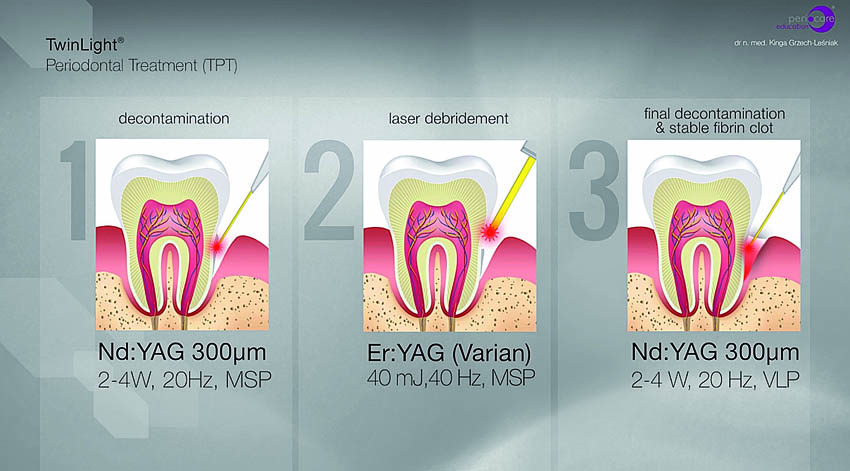

Πριν τη θεραπεία, η ασθενής υποβλήθηκε σε διαδικασία υποουλικού καθαρισμού με ξέστρα υπερήχων. Μετά τον καθαρισμό, η κλινική κατάσταση της ασθενούς βελτιώθηκε. Στη συνέχεια, εφαρμόστηκε ένα laser Nd:YAG για την αποστείρωση και την απολύμανση των περιοδοντικών θυλάκων (Εικ. 3 έως 7) και laser Er:YAG για την απομάκρυνση της υποουλικής τρυγίας (Εικ. 8 έως 12).

Για την τελική απολύμανση και αποστείρωση του πήγματος ινικής, εφαρμόστηκε και πάλι το laser Nd:YAG (Εικ. 13 και 14). Στην Εικ. 15 φαίνεται η κατάσταση αμέσως μετά τη χειρουργική με laser Er:YAG και την απολύμανση των περιοδοντικών θυλάκων με Nd:YAG